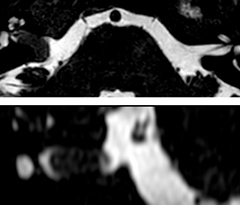

A two year follow-up scan of a CPA meningioma using both Ingenia 3.0T without CS and Ingenia Elition 3.0T with Compressed SENSE allows for a nice comparison to demonstrate the protocol improvements achieved on the Elition: 3D FLAIR has a shortened scan time, improved SNR and still the same spatial resolution. BrainView (3D T1 TSE) has improved spatial resolution and SNR with shortened scan time. For 3D T2 Drive the spatial resolution has been improved. 3D THRIVE used to have an interpolated 0.8 mm slice thickness, but true thickness at 1.6 mm, so that axial slices displayed a decent quality, but reformats were suboptimal. Compressed SENSE is used on Elition to improve spatial resolution and reduce the non-interpolated slice thickness to allow smoothly reformatted images. Total scan time (adding SmartBrain and an additional b2000 diffusion) was 13:19 on Ingenia, and is now reduced to 10:42 on Ingenia Elition.

Ingenia 3.0T (without Compressed SENSE)

3D FLAIR 1.0 x 1.0 x 1.0 mm* 4:24 min.

3D TSE T1w 1.0 x 1.0 x 1.2 mm* 2:40 min.

3D T2w Drive 0.8 x 0.8 x 1.0 mm* 3:05 min.

3D T1w THRIVE 0.8 x 0.8 x 1.6 mm* 1:30 min.

Ingenia Elition 3.0T with Compressed SENSE

3D FLAIR 1.0 x 1.0 x 1.0 mm* 2:50 min.

3D TSE T1w 1.0 x 1.0 x 1.0 mm* 2:10 min.

3D T2w Drive 0.7 x 0.7 x 0.7 mm* 2:52 min.

3D T1w THRIVE 0.7 x 0.7 x 0.8 mm* 1:30 min.

*true voxel size, without interpolation